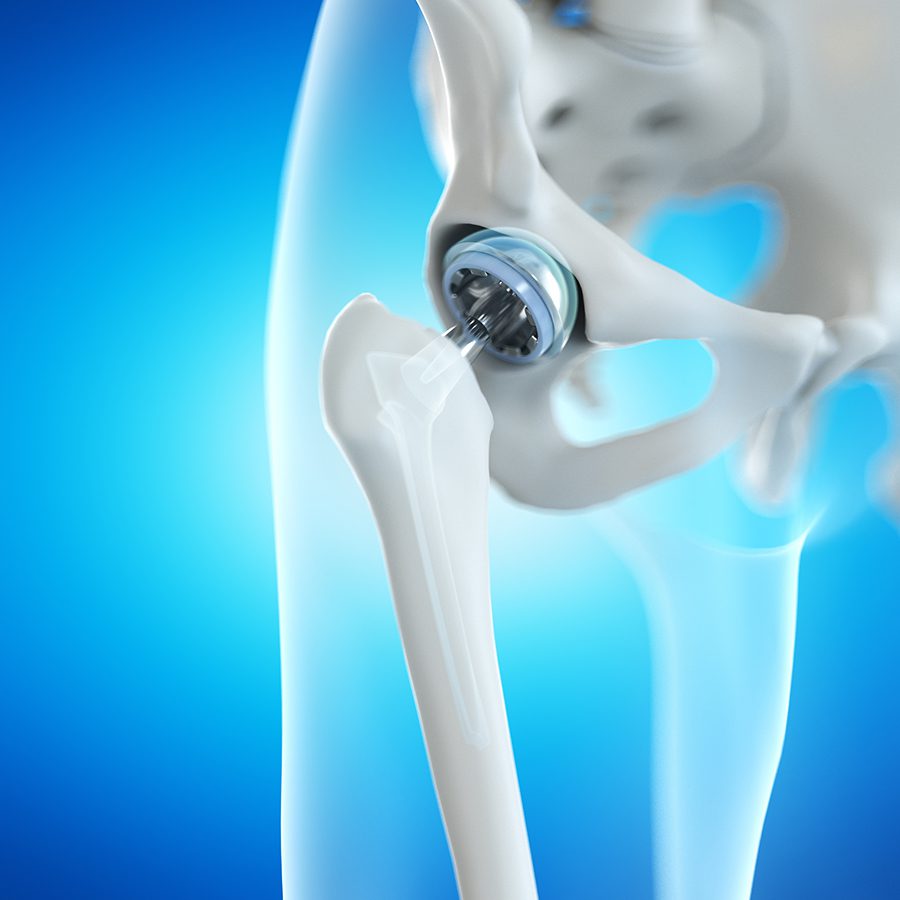

What Is Hip Joint Replacement

What Is Hip Joint Replacement

Total Hip Replacement OrthoSport Victoria